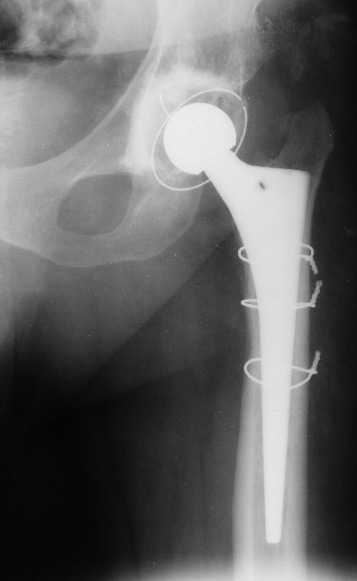

Приведу клинический пример несколько схожий с Вашим. Пациент 56 лет, 18 лет назад получил перелом шейки бедренной кости. Полноценного лечения не получил и остался с неопорным бедром. Укорочение было в районе 6-7 см. Первым этапом после миотомии приводящих мышц в теч. 2-х недель низвели бедро аппаратом Илизарова, далее сняв аппарат установили эндопротез гибридной фиксации (выраженный остепороз впадины ввиду отсутствия нагрузки). К сожалению, в процессе установки ножки эндопротеза произошёл перипротезный перелом медиальной стенки и профилактически мы наложили серкляжные швы. Контроль через 12 месяцев -укорочения нет, функция нормальная. Оперирован в 2005 году. с 2006 года к нам не обращался. АИФ